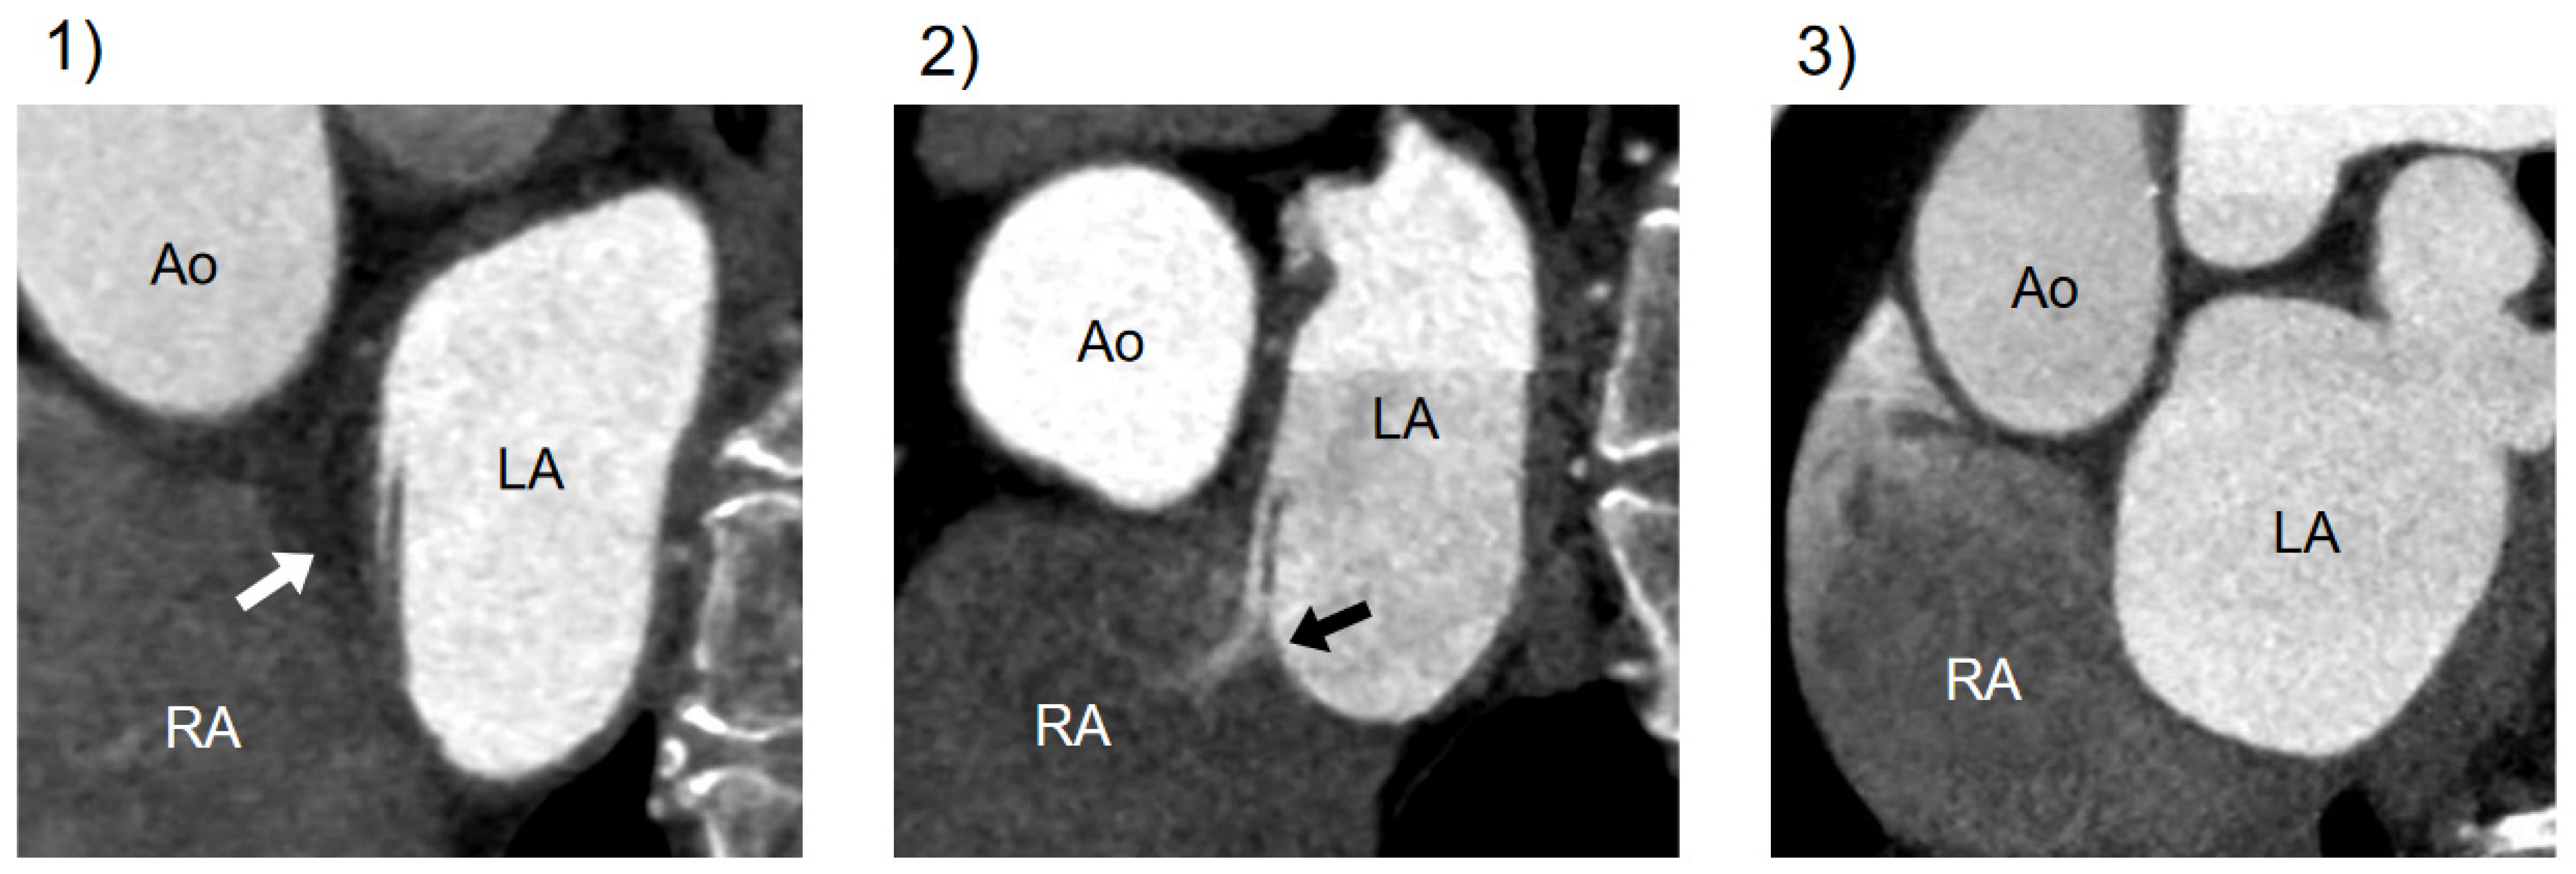

2.3. Assessment of PFO at Cardiac CT

3.4. Comparison of Diagnostic Performance of CT Findings: CLA Alone versus CLA with Jet Flow

| CLA | channel-like appearance |